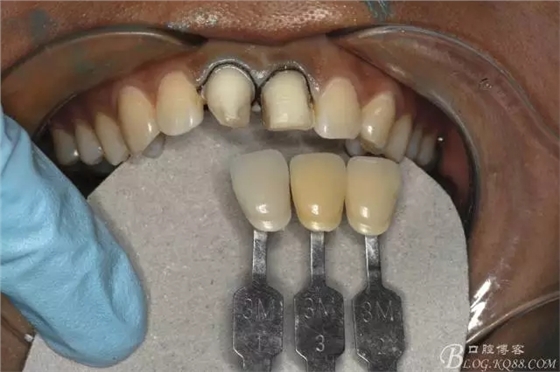

比色